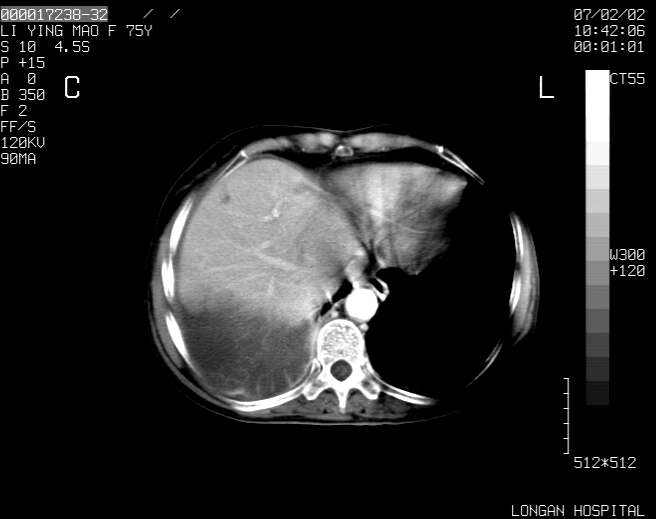

以下是引用dyqct在2007-2-10 8:53:00的发言:[br]考虑:1、肝脏多发囊肿[br] 2、左肾囊肿,右肾多发结石并积水。[br] 3、右胸少量积液。[br] 4、右肾周包裹性积液或淋巴管瘤(有见缝就钻的征象、薄隔、小结节状钙化)?[br] 5、腰椎动脉瘤样骨囊肿?[br] [br] [br]